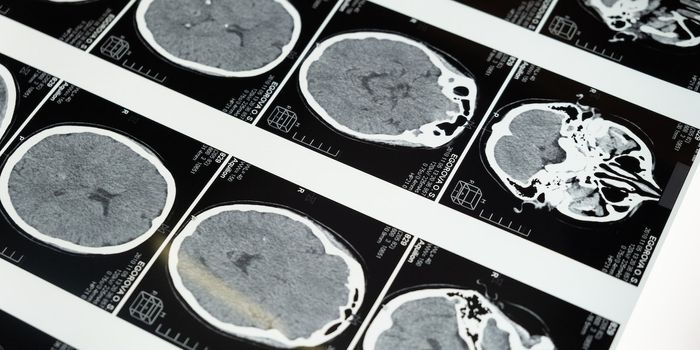

MAR 17, 2024NeuroscienceMild traumatic brain injury (mTBI) from exposure to explosive blasts has been linked to changes in cerebrospinal f ...